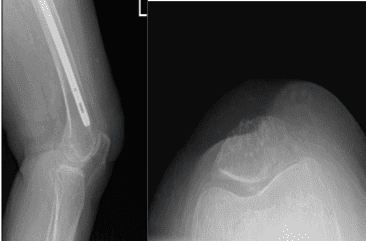

Xray were presented and reviewed, the patient’s femur was healed intertrochanteric fracture but there are mild osteoarthritic degenerative changes found on her knee. We discussed the possibility of etiology of knee pain and treatment options.

Left Knee X-ray Complete with Patella

Left Knee X-ray AP and Lateral with Oblique 3 views